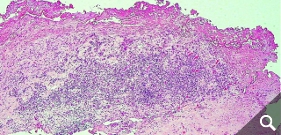

Skin tests (epicutaneous tests) do not show a clear correlation to the reaction of a joint to the implant, so that even skin testing for a metal or cement allergy cannot give a 100% indication. Therefore, in case of doubt, it is necessary to perform a tissue biopsy from the affected joint to provide the appropriate level of certainty. In the case of an allergy, lymphocyte infiltrates are frequently found in these tissues.